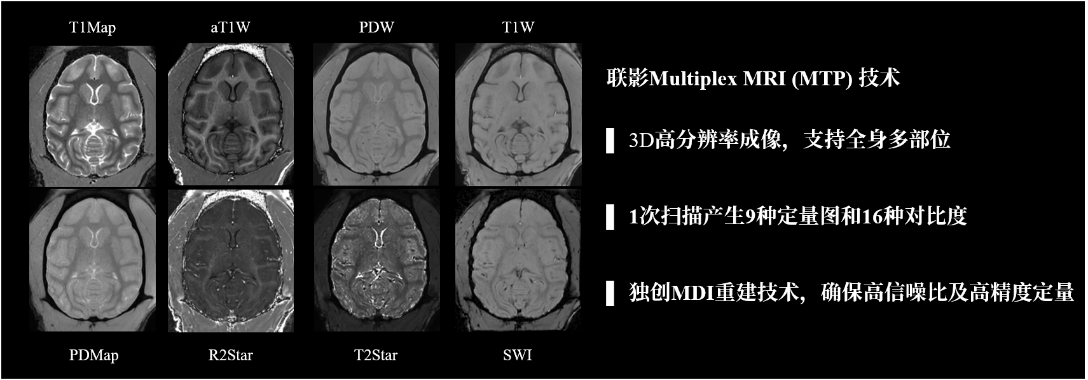

Multiplex (MTP)是联影独家研发的3D多参数定量磁共振成像方案,从序列设计到图像重建进行了全流程创新,使 MTP 通过单次快速扫描便能够得到包括 T1 Mapping、T2* Mapping、PD Mapping、QSM 等多种定量图以及 aT1W、SWI 等多种加权图,实现了一次扫描产生多种对比度图像的效果,有助于科研工作者从多角度研究模式动物组织的不同特性。